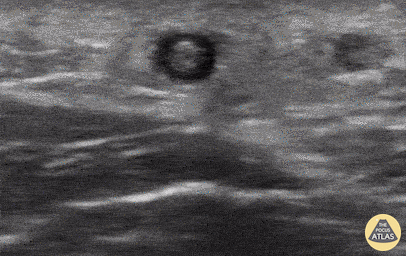

A patient presented reporting a tender, erythematous, and edematous portion of his left forearm; notably at the site of an IV that had been in place at the time of a recent surgery. POCUS as seen here revealed a hyperechoic area within a vessel concerning for thrombus, consistent with the diagnosis of superficial thrombophlebitis. Point of care ultrasound can be useful in differentiating thrombophlebitis from other differential diagnoses including muscle strain or sprain. Rupinder Sekhon, MD Central Michigan University, Emergency Medicine